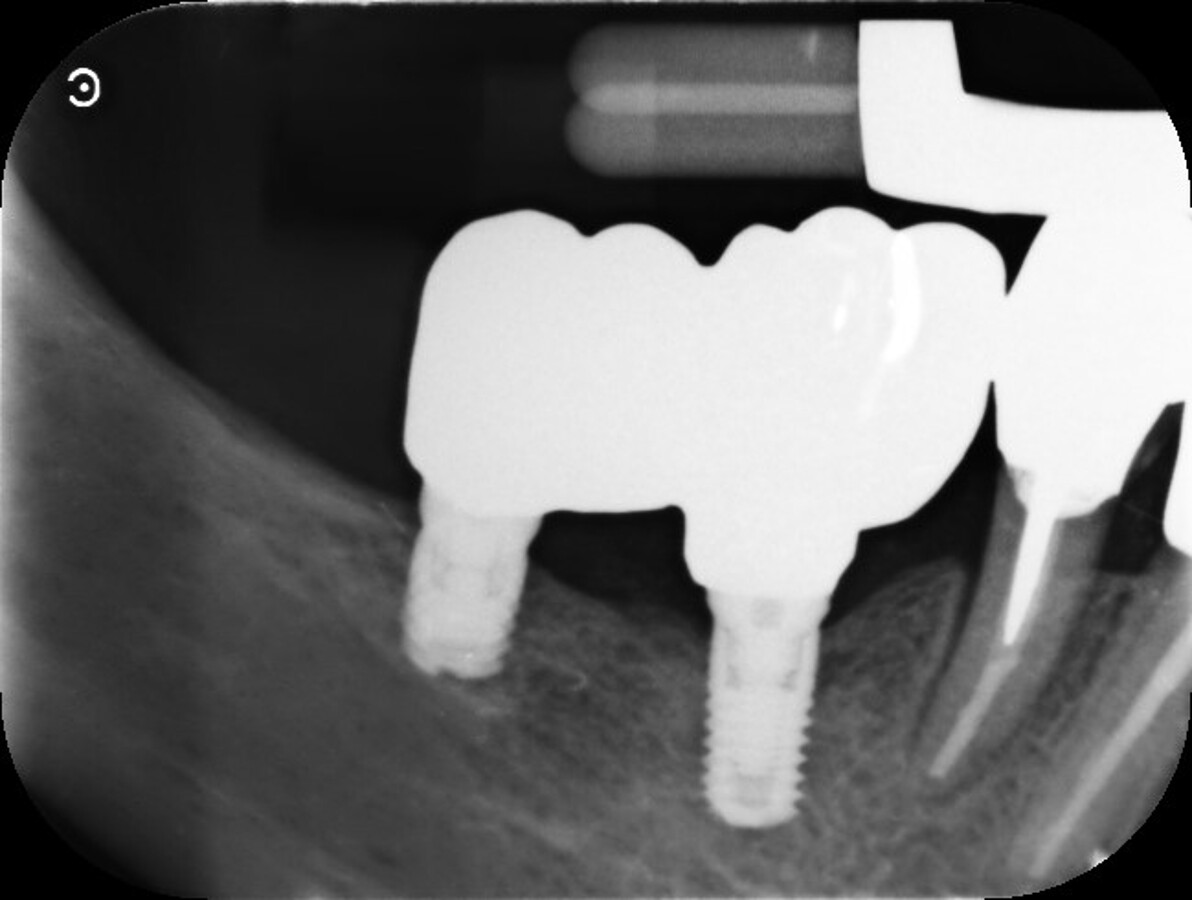

La terapia anticoagulante non è stata interrotta prima della chirurgia ed è stata somministrata la profilassi antibiotica come da protocollo. È stata eseguita un’incisione crestale senza tagli di scarico che è stata estese distalmente fino al trigono retromolare per esporre la branca mandibolare ed avere un sito per raccogliere osso autologo con una fresa carotatrice. Sono state eseguite le osteotomie a basso numero di giri come da protocollo BTI per ottenere un’ulteriore quantità di osso autologo raccolto dalle frese e inseriti due impianti BTI Core 3,75 x 4,5 e 3,5 x 6,5 rispettivamente in posizione 46 e 45.

L’osso autologo è stato mescolato con gel piastrino ottenuto da centrifugazione del sangue del paziente mediante metodica Endoret BTI. La membrana ottenuta è stata applicata a protezione della corticale vestibolare. Ulteriori membrane di gel piastrino sono state applicate sopra l’osso autologo. La stabilita primaria di entrambi gli impianti era superiore ai 50 Newton per cui sono stati avvitati i pilastri Multi-Im e i pilastri di guarigione per un tecnica con una sola chirurgia. Sono state applicate suture sintetiche non riassorbibili a punti staccati (Figg. 3–10). Successivamente è stata eseguita una Rx di controllo. Le suture sono state rimosse a due settimane e la paziente riferì di avere avuto disagi minimi, senza ematomi o edemi estesi e scarsa dolenzia che non richiese l’assunzione di antinfiammatori.

A sei mesi dalla consegna delle corone è stata eseguita un Rx endoorale di controllo da cui si evidenziava una buona stabilità dell’osso marginale (Fig. 11).